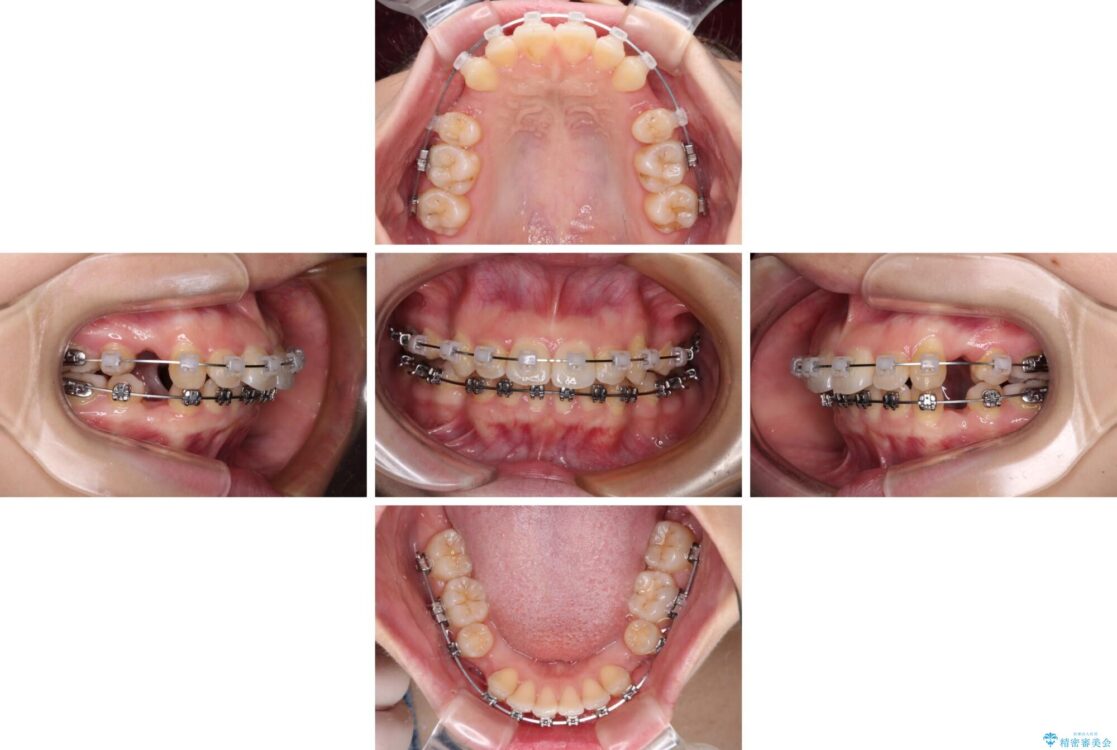

治療途中

• 【モニター】口が閉じられない ワイヤー装置での抜歯矯正 治療途中画像